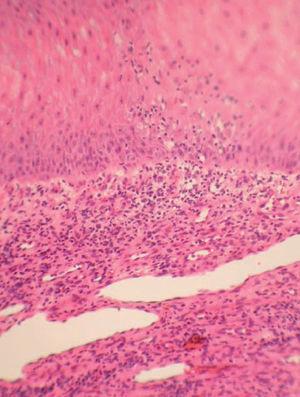

Se realizó una biopsia cutánea de la lesión (fig. 2).

Fig. 2.—Detalle histológico de la lesión. (Hematoxilina-eosina, ×400.)

En el examen histopatológico (fig. 2) se observó una epidermis acantósica y papilomatosa, hiperqueratosis y paraqueratosis, así como vacuolización de las células del estrato de Malpighi, algunas de las cuales presentan inclusiones eosinofílicas intracitoplasmáticas. En la dermis había un denso infiltrado mononuclear con exocitosis epidérmica focal y notoria proliferación de vasos sanguíneos.

Los cambios histopatológicos se corresponden con las manifestaciones clínicas observadas; en todas las fases de la enfermedad pueden verse cambios citopáticos epidérmicos. En general, se caracteriza por una epidermis con marcada hiperplasia pseudoepiteliomatosa, balonización e inclusiones eosinófilas intracitoplasmáticas. En dermis existe una gran dilatación y proliferación vascular junto con un infiltrado inflamatorio agudo o crónico, según el estadio evolutivo3,7.